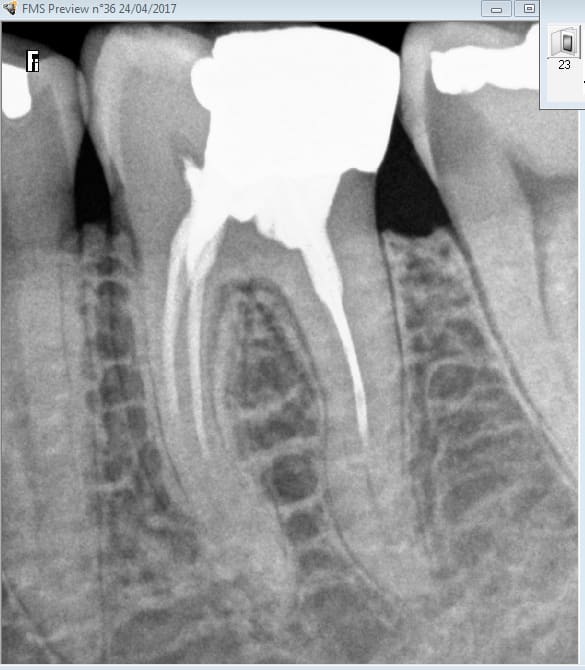

Alleeeez je peux pas résister. Nouveau patient bilan radio + endo 46 ( pas mal pour un premier RDV de 30 minutes). Bon j'avoue j'ai débordé de 10 mn.

Tiens casa a fait l'endo de 36 ? Pas de couronne dessus c'est tout à ton honneur. -)

Tu vois par exemple casa n'aurait pas soigné cette 37 juste derrière le merveilleux traitement endo de 36. parce que casa n'aurait pas fait de rétro coronaire. Que va il se passer endo ou pas ? A vrai dire j'en sais rien tout dépend de si effraction pulpaire ou pas lors du nettoyage de la cavité ca a l'air limite. -)

Tu vois je ne couronne pas toutes les dents dévitalisées. Seulement celles qui présentent des signes d'appel. J'ai beau aimer l'endo un RTE n'est jamais gagné d'avance. -)

Mais on peut etre rentable en endo sans couronner dessus. la preuve. -)

Et puis ca rend tellement service au patient. -)